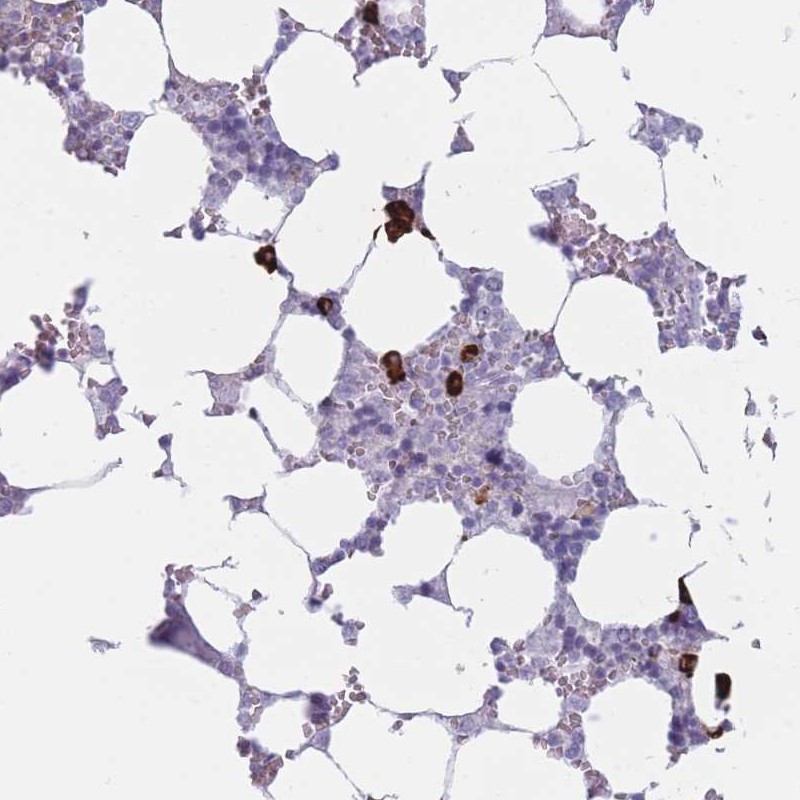

Immunohistochemical staining of human bone marrow shows strong cytoplasmic positivity in subset of hematopoietic cells.